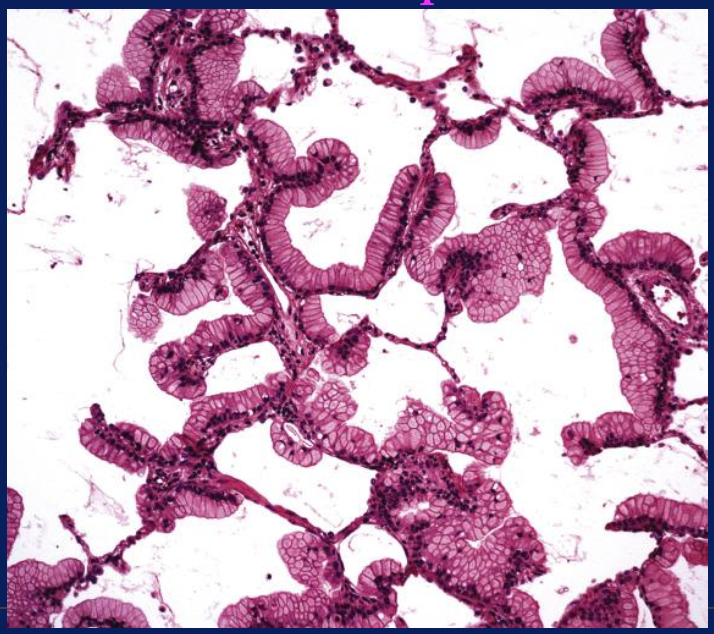

Patrón de adenocarcinoma

Lepídico, reviste la superficie de paredes alveolares, preservando arquitectura pulmonar

<p>Patrón de adenocarcinoma</p>

Patrón lepídico mucinoso